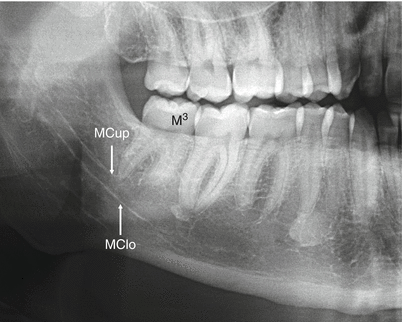

mandibular canal

tubelike passageway thru bone that travels within body or length of mandible

radiolucent band outlined by two thin radiopaque lines representing cortical walls of cancal, may be seen on intraoral